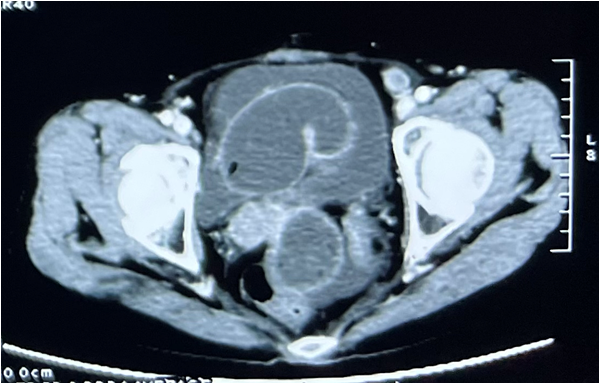

患者为60岁女性,4年前因发现右附件区占位,限期在外院行腹腔镜探查+经腹全子宫切除+双侧附件切除+盆腔粘连松解术+大网膜切除术+阑尾切除术+盆腔淋巴结清扫术。术后病理提示:卵巢子宫内膜样腺癌,网膜组织及乙状结肠浆膜面见癌细胞累及,腹水见恶性肿瘤细胞,淋巴结均未见癌细胞转移。术后予以6次TC方案化疗。2月前患者因腹痛再次入院,查腹部增强CT提示:1)卵巢癌术后改变,盆腔转移可能性大,累及右侧输尿管下段。2)右侧输尿管及右肾积水扩张,右肾功能受损。肠梗阻改变。3)支气管炎伴感染,左肺小结节影。4)盆腔积液,直肠壁增厚。5)左侧中下腹小肠壁增厚。经MDT讨论,考虑患者目前盆腔恶性肿瘤复发侵犯输尿管及肠道,拟行腹腔镜探查,备盆腔肿瘤切除+小肠部分切除术+小肠造口术+经尿道输尿管置管术。

图1术前腹部CT